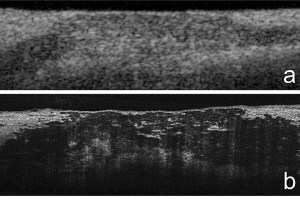

A closer look at atherosclerosis

Researchers at the Wellman Center for Photomedicine at Massachusetts General Hospital (MGH) have developed a one-micrometer-resolution version of the intravascular imaging technology optical coherence tomography (OCT) that can reveal cellular and subcellular features of coronary artery disease.